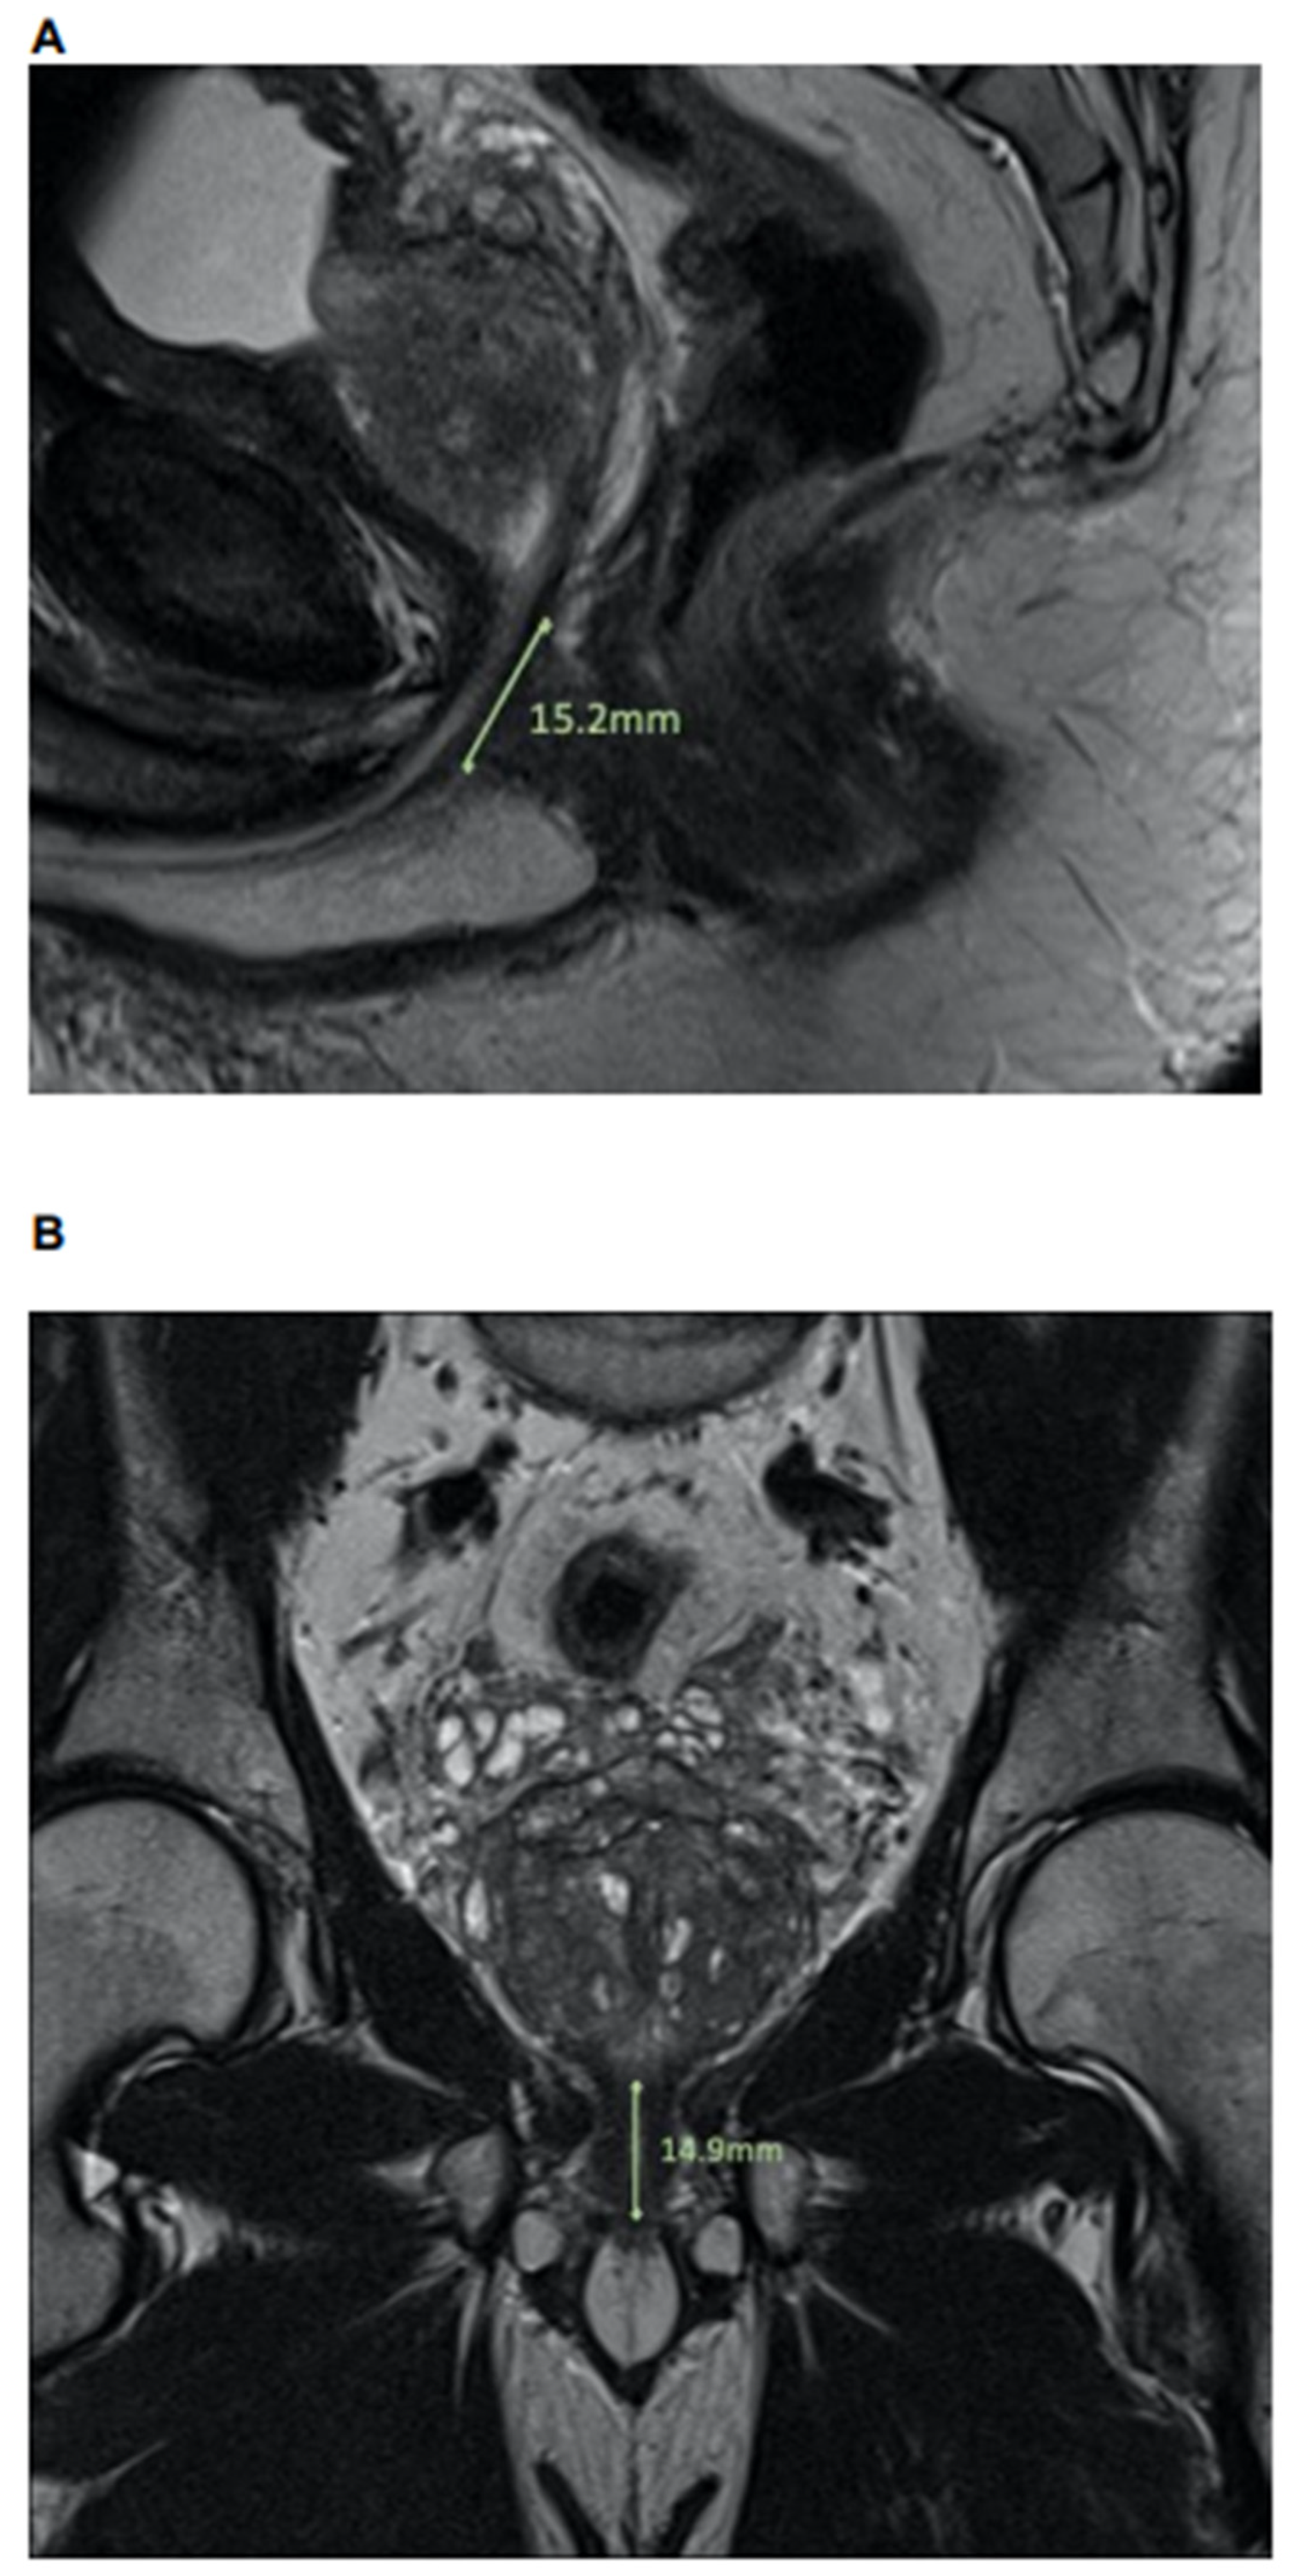

2.2. MpMRI: Lee-Type Definition and Urethral Sphincter Length

Length of urethral sphincter, coronal, in mm Median (IQR) | 14.7 (13.0, 16.7) | 15.0 (13.7, 17.1) | 14.5 (12.2, 16.2) | 0.2 |

Length of urethral sphincter, coronal, in mm Median (IQR) | 14.7 (13.0, 16.7) | 15.1 (13.8, 16.9) | 12.5 (11.9, 14.2) | 0.009 |